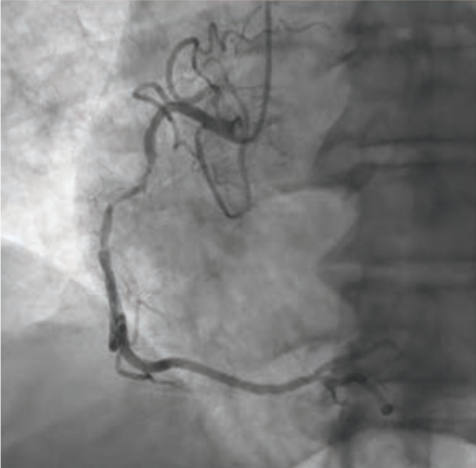

“Over the years as an interventionalist, writes Dr. Jeffrey Cook in Quincy, Illinois, “I have noticed a patient profile of an individual presenting somewhat late into their myocardial infarction (MI) — 12-24 hours or so — who seems to be overtly stable as they arrive at the emergency department (ED). Minimal pain, hemodynamics normal (or even hypertensive), oxygenation normal, no indication of decompensation noted. Everything seems perfectly routine. The patient is brought to the cath lab, the infarct-related artery is identified, wired, and ballooned — and from there, the patient decompensates. Even though the vessel has gone from 100% to 0%, suddenly the patient is hypotensive, with progressive respiratory distress, and progressing to shock. I have unfortunately been fooled by this presentation (Figures 1-4) many times, and I’m wondering a few things. First, what is the mechanism? Is it something to do with sudden washout of acidotic myocardium? Second, is there any way to predict that this is going to happen, and to take measures to prevent it? I recently had a patient present like this again, and I find myself extremely frustrated and distraught about it. Can you provide some guidance or direct me to appropriate literature? I’ve tried to find articles or even discuss it with other operators and have been stymied. I did find a thoughtful article by Yongbin Li et al,1 but it does not necessarily answer my questions.”